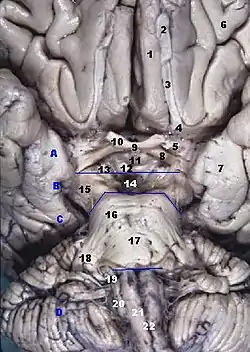

Human brainstem anterior (piriform cortex not labeled, but most of it is visible near #7) | |

In human anatomy, the piriform cortex has been described as consisting of the cortical amygdala, uncus, and anterior parahippocampal gyrus.[1] More specifically, the human piriform cortex is located between the insula and the temporal lobe, anteriorly and laterally of the amygdala.[2][3]